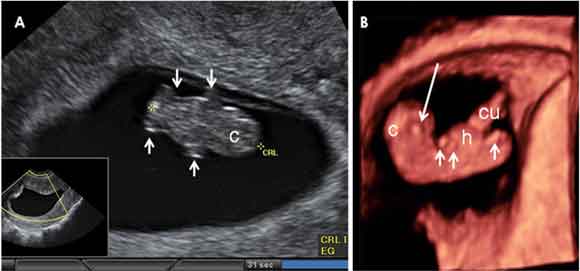

Ecografía en 2D y 3D de embarazo de 8,1 semanas. El embrión mide 17 milímetros. En A) proyección frontal, donde se distinguen los esbozos de las cuatro extremidades (flechas cortas) y el polo cefálico (c). En B) proyección sagital, con el perfil del embrión mostrando una curvatura importante en la cabeza (c) y el extremo caudal afilado. El cordón umbilical (cu) se inserta en una especie de esfera que abulta por delante del abdomen (h), donde están las asas intestinales. En el extremo correspondiente a la cabeza se distingue la estructura primitiva de un globo ocular (flecha larga).